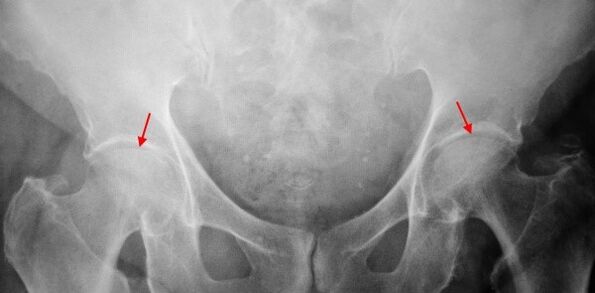

Concerning the X - -caring of the patient suffering from first -degree grining, mild changes are determined: moderately uneven stenosis of the joint gap, as well as bone developments around the outer or inner edge of the acetabular absence of changes from the head and neck of the bone.

In pictures X for the 2nd degree body, a significant heterogeneous narrowing of the joint gap is determined (more than half of the normal height).The femoral head is somewhat shifted upwards, deformed and increases in size and its contours become heterogeneous.Bone increases with this degree of trunk occur not only on the inside but also on the outer edge of the acetabular and to get out of the cartilage.

In the 3rd degree x -rays for the 3rd degree body, a sharp narrowing of the joint gap, a strong extension of the thigh head and multiple bone increases are detected.

The diagnosis of carxars is based on clinical symptoms and data of additional studies, the main of which is radiography.In many cases, the X -rays make it possible to establish not only the grade of the trunk but also the cause of its appearance.Thus, for example, the increase in the corner-corner angle of the throat, scenes and leveling of the acetabular indicate malformation and changes in the shape of the near part of the thigh indicate that grains is a consequence of peeres or youthful disease.In radiographs of patients with crothaul, changes that indicate injuries may also be detected.